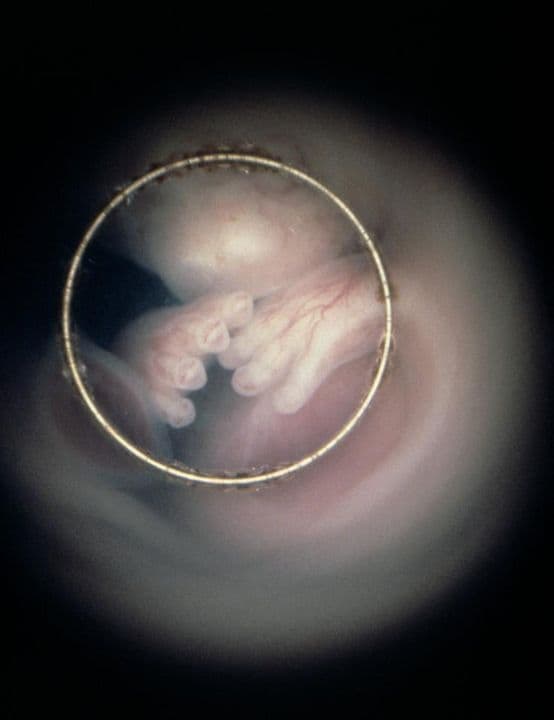

This endoscopic image, obtained by passing a fine light-emitting tube into the uterus, shows the hands obscuring the fetus’s face.

Your baby’s limbs are more developed now, enabling him to move, and his hands and fingers can be clearly seen on a scan.